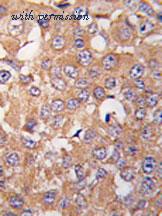

- Plk2 antibody